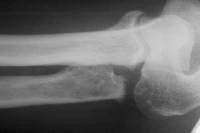

This patient had undergone a radial head excision as primary treatment for his radial head fracture.

Prior radial head excision.